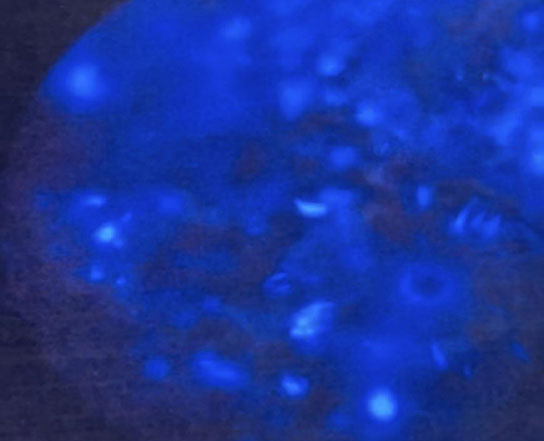

After one hour, the tetracycline-infused specimen displayed patchy yellowish-green fluorescence under UV light (Fig. 5, Supplementary Video 3).

Yellowish green calcification under ultraviolet (UV) light.

(Supplementary Video 3: Tetracycline labelling revealed yellowish green areas of calcification under ultraviolet light)

Alizarin Red staining produced orange deposits under green light illumination (Fig. 6, Supplementary Video 4). No regional dominance of labeling (superior vs. inferior) could be determined with either tetracycline or alizarin red dye.

Orange calcification deposits under green light.

(Supplementary Video 4: Alizarin red staining revealed orange calcification deposits under green light in the femoral neck)